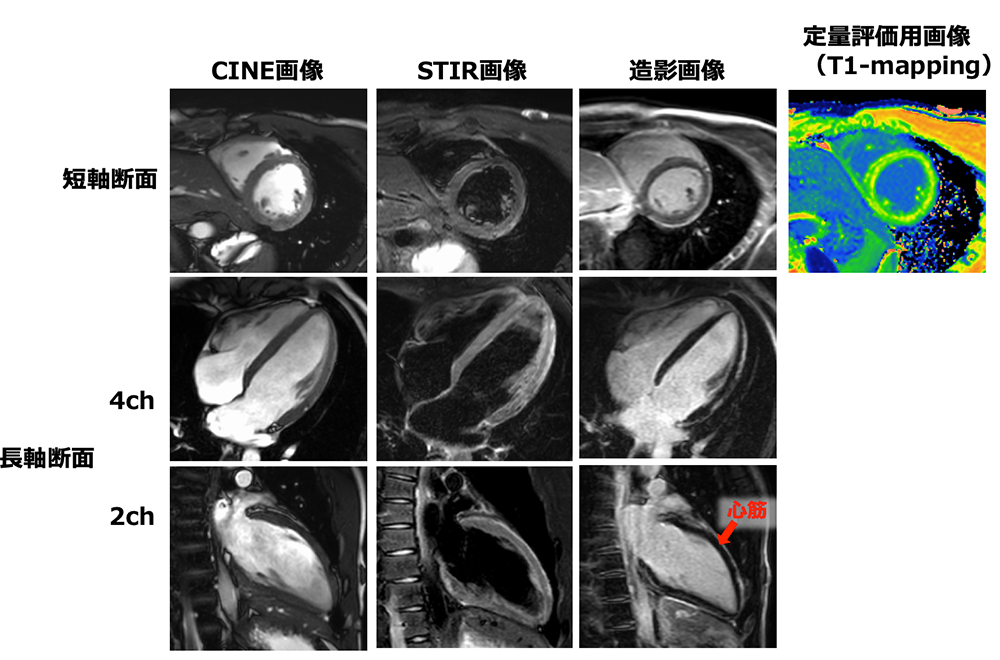

心臓MRIは、心臓の動きを動画(CINE画像)で撮像することができ、心機能の解析が可能です。STIR画像では心筋が炎症を起こしていないか、造影画像では、治療を行うことにより心臓が改善するかを評価します。